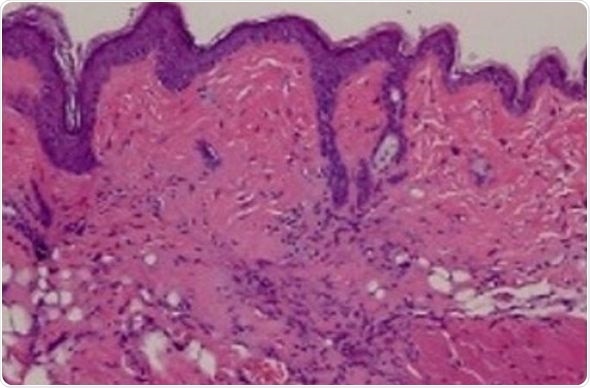

The team first analyzed skin biopsies from scleroderma and non-scleroderma patients to see if the TRAIL protein and other proteins it associates with are present. They found that while non-scleroderma skin biopsies contained low levels of TRAIL and other associated proteins, skin from patients with scleroderma contained far higher levels of TRAIL and associated proteins.

The second type of mice they tested were genetically engineered to have the skin fibrosis associated with scleroderma but without the severe inflammation that produces the fibrosis. These mice develop scleroderma-like skin when they’re 4 to 5 weeks old. The researchers started treating the mice at 5 weeks of age every other day for five weeks and then evaluated the skin of the treated versus untreated mice. They found that untreated mice had thickened skin and collagen deposits similar to human scleroderma, whereas treated mice showed molecular signs of dying cells with significantly less skin fibrosis. “These data say to us that TRAIL could potentially reverse skin fibrosis to near normal skin,” says Lee.